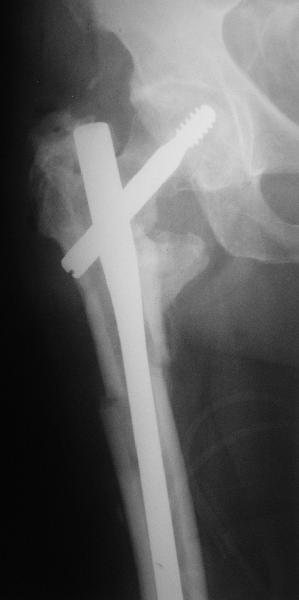

На прошлой неделе оперировали похожего пациента. 2 года после неудачного остеосинтеза PFN в другом регионе. После удаления остатков железа выявилось несращение вертельной области.

Если есть сильное желание фиксировать все-таки гвоздем, советовал бы ввести мощный "джойстик" параллельно оси шейки бедра близко к ее задней стенке, сделать поперечную межвертельную остеотомию и использовать дистрактор таз-бедро.

Поскольку в нашем случае выявилась подвижность, мы наложили дистрактор таз-бедро на 3 дня, и сделали остеосинтез гаммой без остеотомии. То, что произошла "корригирующая остеоклазия" в подвертельной области, выявили после введения гвоздя. Пациент уже уехал домой, будем наблюдать.